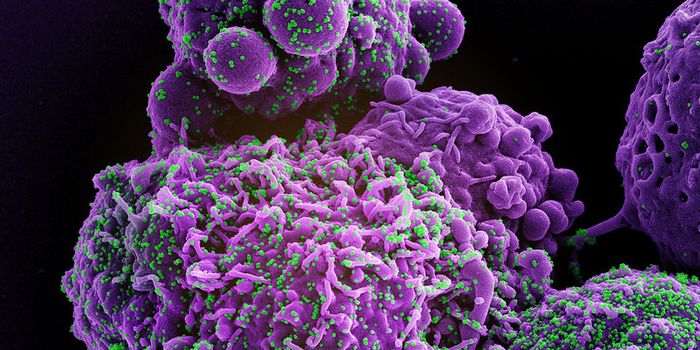

MAR 28, 2024CancerPublic domain via Wikipedia. Source: NIH Author: National Library of Medicine As we near the close of W ...

MAR 25, 2024CancerAcute myeloid leukemia (AML), a cancer that develops in the bone marrow and blood when immature white blood cells called ...

MAR 14, 2024CancerCompared to White men, Black men have a higher risk of developing prostate cancer. Additionally, Black men have a ...

MAR 12, 2024CancerIn addition to the emotional and physical complications that go hand in hand with a cancer diagnosis, there is often the ...

MAR 11, 2024CancerImmune checkpoint inhibitors (ICIs) have made remarkable progress in combating cancer. Two ICIs which target the p ...

MAR 04, 2024CancerCervical cancer, which develops in the lower portion of the uterus, known as the cervix, typically grows slowly. C ...

FEB 29, 2024CancerWe focus on a lot of studies investigating metastatic cancer, a disease that occurs when cancer cells spread from their ...

FEB 26, 2024CancerChronic, or long-term stress can lead to a multitude of illnesses and diseases, including digestive issues, heart diseas ...

FEB 21, 2024CancerLast August, Labroots covered the decision of the National Health Service of England (NHS England) to allow subcu ...

FEB 12, 2024CancerCervical cancer incidence rates in the United States declined substantially between the 1970s and 2000s, due in part to ...

FEB 09, 2024CancerChemotherapy-induced peripheral neuropathy (CIPN) remains a significant challenge in cancer treatment, particularly with ...

FEB 09, 2024CancerHistopathology describes the process of examining pieces of tissue using a microscope. Light microscopic (LM) exam ...

FEB 05, 2024CancerLet’s start with some good news: the number of cancer survivors in the United States continues to grow due to impr ...

FEB 01, 2024CancerThe circadian clock describes the 24-hour internal clock in our brains. The rhythms that regulate our awake and sl ...

JAN 29, 2024CancerColorectal cancer (also called bowel cancer) typically develops in the large bowel (colon) or rectum. Recent studi ...

JAN 21, 2024CancerEach year, the American Cancer Society (ACS) publishes comprehensive estimates of the cases and deaths of every type of ...

JAN 18, 2024CancerVaccines play an important role in public health as well as our health and well-being. Babies often get various va ...

JAN 15, 2024CancerThe 2014 passage of the Patient Protection and Affordable Care Act (ACA) allowed states to expand Medicaid benefits by m ...

JAN 11, 2024CancerA commonly used biopsy technique, known as a percutaneous or needle biopsy, involves inserting a small needle under the ...

JAN 08, 2024CancerA recent study published in JAMA Network Open has concluded significant racial disparities exist within the National Can ...

JAN 04, 2024CancerThe most common type of adult liver cancer, hepatocellular carcinoma (HCC), accounts for about 90% of liver cancer diagn ...

JAN 02, 2024CancerImmunotherapies have drastically improved the array of treatment options available for cancer patients. In contras ...

DEC 18, 2023CancerNeuroblastoma, a cancer that forms in immature nerve cells, most commonly occurs in young children under the age of five ...

DEC 11, 2023CancerOncologists have used radiation therapy for over a century to treat various types of cancer. In brief, radiation t ...

DEC 07, 2023CancerCervical cancer remains a significant clinical challenge globally, as evidenced by over 600,000 new diagnoses and over 3 ...

DEC 05, 2023CancerDesmoid tumors are a type of rare and challenging medical condition with an incidence of approximately 3-5 cases per mil ...

DEC 04, 2023CancerMesothelioma, a type of lung cancer highly associated with asbestos exposure, has a five-year survival rate of only 10%. ...

NOV 30, 2023CancerCytotoxic T cells (CTLs), a type of immune cells integral to fighting cancer, rely heavily on interaction with a molecul ...

NOV 27, 2023CancerThe US Centers for Disease Control (CDC) estimates that nearly 50 million people (about 18% of Americans) have used cann ...

NOV 22, 2023CancerTomorrow, many in the United States celebrate Thanksgiving, a holiday occurring on the fourth Thursday each November.&nb ...

NOV 16, 2023ImmunologyCancer is very difficult to treat due to various components that therapies must address to effectively kill or lyse tumo ...

NOV 16, 2023CancerThe links between tobacco use and cancer shouldn’t come as a big surprise to most Labroots readers. Tobacco ...

NOV 13, 2023CancerDifferent species have evolved to process certain senses better than other species. For example, humans can hear f ...

NOV 11, 2023CancerToday marks Veterans Day in the United States, a celebration of the men and women who have served and sacrificed for thi ...

NOV 07, 2023CancerIf you have paid attention to medical news lately, you have almost certainly heard about some emerging uses of artificia ...

NOV 06, 2023CancerWith Breast Cancer Awareness Month (October) having just passed, it is notable to express how formidable of an adversary ...

OCT 31, 2023CancerToday, we celebrate Halloween, a holiday originating from the ancient Celtic festival of Samhain. Some 2,000 years ...

OCT 30, 2023CancerMammography, an X-ray imaging technique, represents a highly effective method of detecting breast cancer. Receivin ...

OCT 27, 2023CancerExperts estimate nearly 14,000 new cases of cervical cancer in 2023 in the United States. In addition, we will see ...

OCT 19, 2023CancerA Pap smear, also called a Pap test or a Papanicolaou test, describes a procedure that removes cells from the surface of ...

OCT 17, 2023CancerCutaneous squamous cell carcinoma (cSCC) is a common form of skin cancer often caused by chronic exposure to ultraviolet ...

OCT 09, 2023CancerRadiotherapy (also called radiation therapy), a commonly used cancer treatment that uses high-energy radiation, can effe ...

OCT 05, 2023Cancer“Cancer” is not a word we want to hear. Conversations with your doctor about cancer can induce fear, a ...

OCT 02, 2023CancerThe Lancet, a prominent medical journal, initiated a Commission to understand the interactions between women, power, and ...

SEP 28, 2023CancerGuidance and recommendations for prostate cancer screening have changed over the years. While there is no standard ...

SEP 25, 2023CancerA report published earlier this month in BMJ Oncology delivered some concerning statistics. Cancer incidence in yo ...

SEP 19, 2023CancerNatural killer (NK) cells represent an important class of immune cells involved in anti-tumor immunity. Once ident ...

SEP 14, 2023CancerAbout half of the pediatric soft tissue sarcoma diagnosed annually are classified as rhabdomyosarcoma (RMS). These ...

SEP 11, 2023CancerToday marks twenty-two years since the unprecedented September 11th terrorist attacks on the United States. The im ...

SEP 07, 2023CancerObesity, characterized as an abnormally high, unhealthy amount of body fat, has become a common disease throughout the U ...

SEP 04, 2023CancerToday, we commemorate Labor Day, a holiday recognizing the American workforce's contributions toward the United Stat ...

AUG 30, 2023CancerThe National Health Service of England (NHS England), the publicly funded healthcare system serving English residents, h ...

AUG 28, 2023CancerWork presented at this year’s American Society of Clinical Oncology (ASCO) annual meeting included data from a pha ...

AUG 25, 2023CancerOn this day in 1789, George Washington, the first President of the United States, lost his mother to breast cancer. ...

AUG 16, 2023CancerAs we complete our series about clinical trials, we will explore some language often used when discussing research studi ...

AUG 07, 2023CancerAn exciting new cancer drug has recently entered into a phase 1 clinical trial supported by promising pre-clinical work. ...

JUL 13, 2023CancerObesity, a disease characterized by an unhealthy amount of body fat, can put individuals at an elevated risk of other di ...

JUL 04, 2023CancerThe Fourth of July holiday celebrates the day America’s Founding Fathers, representing the 13 colonies, officially ...

JUN 20, 2023CancerThe mortality rate associated with childhood cancers, typically considered those diagnosed in children 14 years and youn ...

JUN 19, 2023CancerImmune checkpoint inhibitors (ICIs) have improved the landscape of cancer research over the past decade. These the ...

JUN 12, 2023CancerIn general, many of us think of cancers as age-related diseases. While cancer and aging are highly interconnected, ...

JUN 04, 2023CancerToday marks a special day dedicated to honoring and celebrating those who have survived cancer. National Cancer Su ...

MAY 29, 2023CancerToday Americans celebrate Memorial Day in honor of military men and women who have lost their lives while serving the Un ...

MAY 26, 2023CancerBaz Luhrmann preached the importance of sunscreen to the ladies and gentlemen of the class of ’99 (and ever ...

MAY 18, 2023CancerMetastatic cancer occurs when tumor cells spread from the original (or primary) cancer site to a distant location. ...

MAY 15, 2023CancerCardiotoxicity, damage to the heart or cardiovascular system, occurs as an unfortunate side effect associated with many ...

MAY 10, 2023CancerYesterday the U.S. Preventative Service Task Force (USPSTF) announced an updated recommendation for breast cancer screen ...

MAY 08, 2023CancerWilms tumor (also known as nephroblastoma), a type of kidney cancer most commonly diagnosed in children under five years ...

MAY 04, 2023CancerThe Healthy People initiative emerged from the US Department of Health and Human Services (HHS) in 1980. Each deca ...

MAY 01, 2023CancerMost testicular cancers begin in germ cells, the cells in the testicles that develop into sperm. These malignancie ...

APR 27, 2023CancerChatGPT (Generative Pre-trained Transformer), artificial intelligence (AI) software that operates like a chatbot, has re ...

APR 25, 2023CancerRenal cell carcinoma (RCC), also known as kidney cancer, forms in the tubules of the kidney, the part of the organ that ...

APR 20, 2023CancerThe bacteria Helicobacter pylori (H. pylori) can infect tissues in the mucosal layer that lines the stomach. ...

APR 13, 2023CancerThe increased incidence rate of pancreatic ductal adenocarcinoma (PDAC), along with its highly aggressive nature and poo ...

APR 09, 2023CancerToday many around the world take part in Easter celebrations. For practicing Christians, Easter Sunday and the day ...

APR 05, 2023CancerThe lungs are a pair of organs in the chest integral for transporting oxygen throughout the body (via inhalation) and re ...

APR 03, 2023CancerWell-documented racial inequities exist when it comes to prostate cancer. Extensive research has shown disparities ...

MAR 21, 2023CancerArtificial grass, known as AstroTurf or simply turf, covers the ground at sports stadiums nationwide. Countless nu ...

MAR 17, 2023CancerToday many will celebrate St. Patrick, the Christian missionary and bishop who would become one of Ireland's patron ...

MAR 09, 2023CancerDevices used to measure biological readouts, known as biosensors, determine the concentration of a particular substance ...

MAR 02, 2023CancerImmunotherapies, cancer treatments that target the immune system, have drastically improved patient care over the past d ...

FEB 27, 2023CancerA study presented in November at the Society for Immunotherapy of Cancer 37th Annual Meeting and published in the Journa ...

FEB 21, 2023CancerIn 1976, the American Cancer Society began to recommend mammograms, X-ray images of the breast, as a tool to diagnose br ...

FEB 20, 2023CancerLast year on Presidents’ Day, we investigated some US Presidents known to have cancer diagnoses. This year, ...

FEB 13, 2023CancerThe bladder is an important, and sometimes underappreciated, organ in the body. Located in the pelvis, the bladder ...

FEB 09, 2023CancerColorectal cancer (CRC) can develop in any part of the colon, the large intestine, or the rectum, the area of the body c ...

JAN 19, 2023CancerEpidemiological evidence has established that race and ethnicity play a role in the incidence of several types of cancer ...